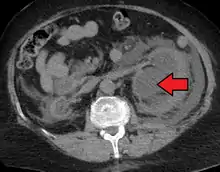

CT scan of bilateral hydronephrosis due to a bladder cancer

Massive hydronephrosis as marked by the arrow.- Renal ultrasonography of hydronephrosis[14]

- Stone causing hydronephrosis[14]

- Urine jets[14]